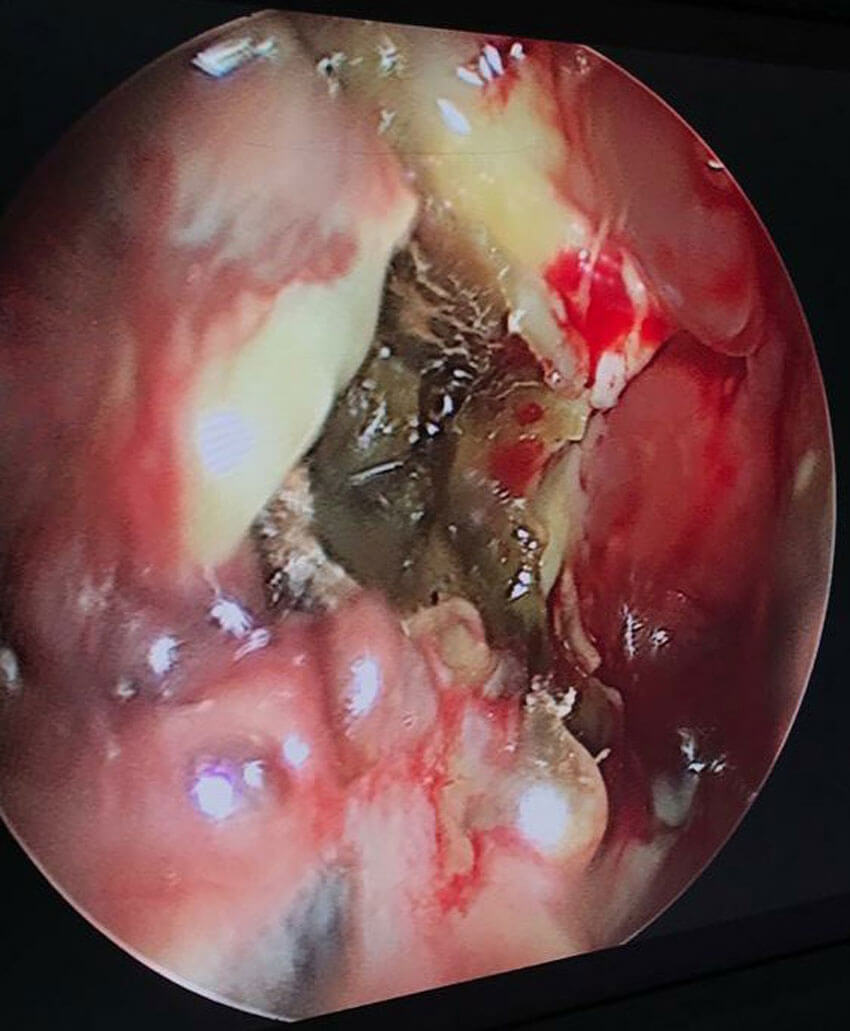

Endoscopic view of pus drained from a frontal lobe abscess through the cribriform plate.

The initial phase saw late presentations including cerebral mucormycosis. But overall, cerebral involvement is about 5-8%. Also, 2-3% of other patients progress to intracranial involvement in spite of aggressive treatment. Cerebritis is managed conservatively with significantly higher doses of amphotericin B. Focal abscesses have been drained by neurosurgeons. About 20% of patients have had some degree of orbital involvement. Surgical management may range from orbital decompression to selective periorbital endoscopic debridement to orbital exenteration (guided by clinical and radiological findings). Most decisions are tailored to the context.